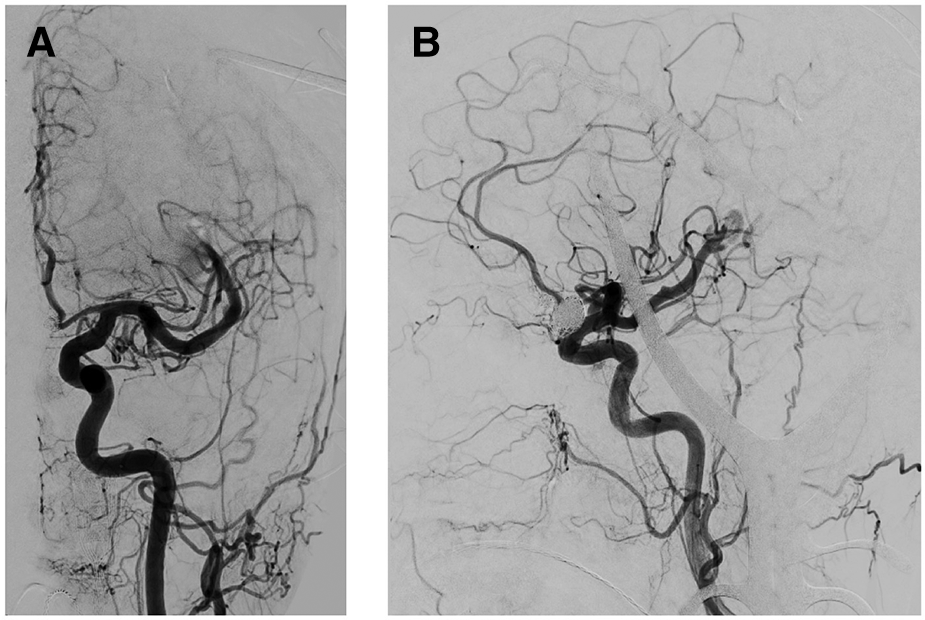

Figure 4

Intraoperative angiogram after BAVM elimination. (A,B) Coronal and sagittal angiogram depicting regression of the flow-related MCA aneurysms following the encounter of BAVM elimination.